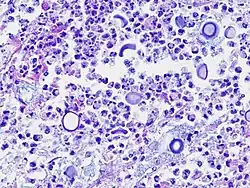

Podstawą szybkiego postawienia diagnozy w wypadku kryptokokowego zapalenia opon mózgowo-rdzeniowych jest badanie płynu mózgowo-rdzeniowego[2]. W pobranej próbce można zazwyczaj zaobserwować podwyższone stężenie białka, obniżone glukozy oraz zwiększoną liczbę leukocytów, głównie jednojądrzastych[2]. W celu wykrycia C. neoformans stosuje się odczyn lateksowy[2]. W badaniu histologicznym tkanek może być widoczna odpowiedź zapalna. W wypadku utworzenia ziarniniaka, komórki C. neoformans można znaleźć wewnątrz komórek olbrzymich[2]. Komórki patogenu można wybarwić hematoksyliną i eozyną, metodą Gomoriego lub mucykarminą, która barwi otoczkę grzyba na kolor jasnoczerwony[2]. C. neoformans można także identyfikować za pomocą immunofluorescencji bezpośredniej[2]. Materiałem do tego badania są skrawki tkankowe umieszczone w formalinie[2]. Wykrycie przeciwciał przeciwko grzybowi w teście immunofluorescencji pośredniej świadczy o przebytym lub trwającym zakażeniu[2]. W celu postawienia rozpoznania zakłada się także hodowlę[4]. Materiałem do hodowli może być płyn mózgowo-rdzeniowy, bioptat lub mocz[4]. U chorych z upośledzoną odpornością, zakażeniem układu nerwowego lub uogólnionym C. neoformans występują w moczu cały czas, nawet gdy nie ma żadnych objawów ze strony układu moczowego[4].